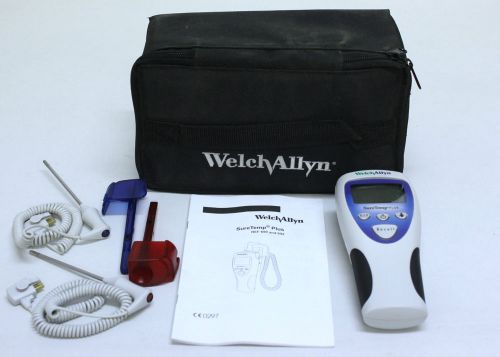

WELCH ALLYN SureTemp Plus 692 Mountable Electronic Thermometer + 2 Probes & Case

New WELCH ALLYN SureTemp Plus Thermometer Probe Well Kit Rectal 4' Red 02892-000

New WELCH ALLYN SureTemp Plus Thermometer Probe Well Kit Oral 4' Blue 02893-000